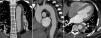

CTA was repeated on the eighth day of hospitalization, and showed a slight increase in hematoma thickness (to around 15 mm), although with no increase in length, and one of the ulcers in the aortic wall appeared deeper and more irregular (Figure 2). The case was again discussed with the cardiothoracic surgical team, and it was decided not to operate and to maintain medical therapy and surveillance. The patient remained clinically stable during hospitalization and was discharged on the 19th day, medicated with four classes of antihypertensive drugs including beta-blockers and referred for outpatient cardiology consultation, and imaging follow-up was scheduled.

Control CTA on the eighth day, showing a slight increase in hematoma thickness to 15 mm and a crescent-shaped formation (C), still extending from the left subclavian artery to the emergence of the renal arteries (A); one of the aortic wall ulcers observed on the initial exam now presenting a deeper and more irregular appearance (arrow) (B).